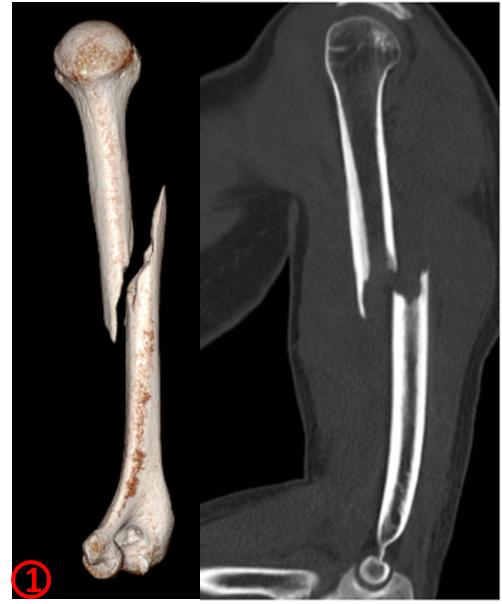

完善血常規(guī)、肝功、鈣磷代謝、尿常規(guī)檢查未見明顯異常,完善肱骨三維CT示右肱骨干病理性骨折(圖1)。